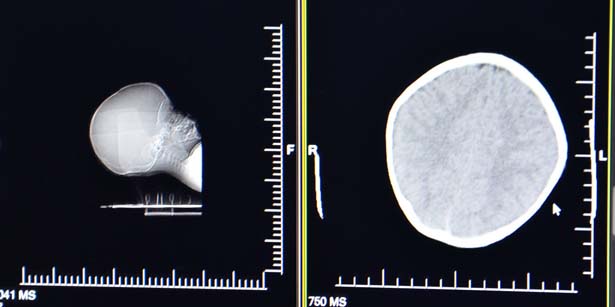

Doktorların morlukları fark etmesi üzerine araştırmanın boyutunun derinleştirildiğini ifade eden BEÜ Hastanesi Başhekimi Doç. Dr. Bekir Hakan Bakkal, "Beyin kanamasıyla Kocaeli'de hastaneye başvuran hastaya çocuk bakım ünitesinin yetersizliğinden dolayı üniversitemiz bünyesindeki çocuk yoğun bakım ünitesine yönlendirildi. 112 acil üzerinden hasta bize başvuruldu. Çocuğun ilk yapılan muayenesinde ufak bir kanama olduğu saptandı. Cerrahi bir müdahale düşünülmedi. Şu an yoğun bakım ünitemizde tedavisi devam ediyor. Genel durumu geldiği zamana göre daha iyi. İnşallah yakın zaman içerisinde genel durumunu toparlayıp sağlığına kavuşturacağız. Çocuğun vücudunda gerek yüz çevresinde gerek gövdesinde bazı morlukları mevcut. Ama bununla ilgili uzmanlarımız değerlendirecekler. İşin hukuki boyutu da var gibi gözüküyor. Bununla ilgili olayın detayları şekillendikçe daha net bir aşamaya gelinecek. Yüzde ve vücutta eski ve yeni olma olasılığı bulunan bazı morluklar mevcut. Bununla ilgili uzman arkadaşlarımız bazı detaylı inceleme yapacaktır ve biraz daha açıklığa kavuşacaktır" şeklinde konuştu.